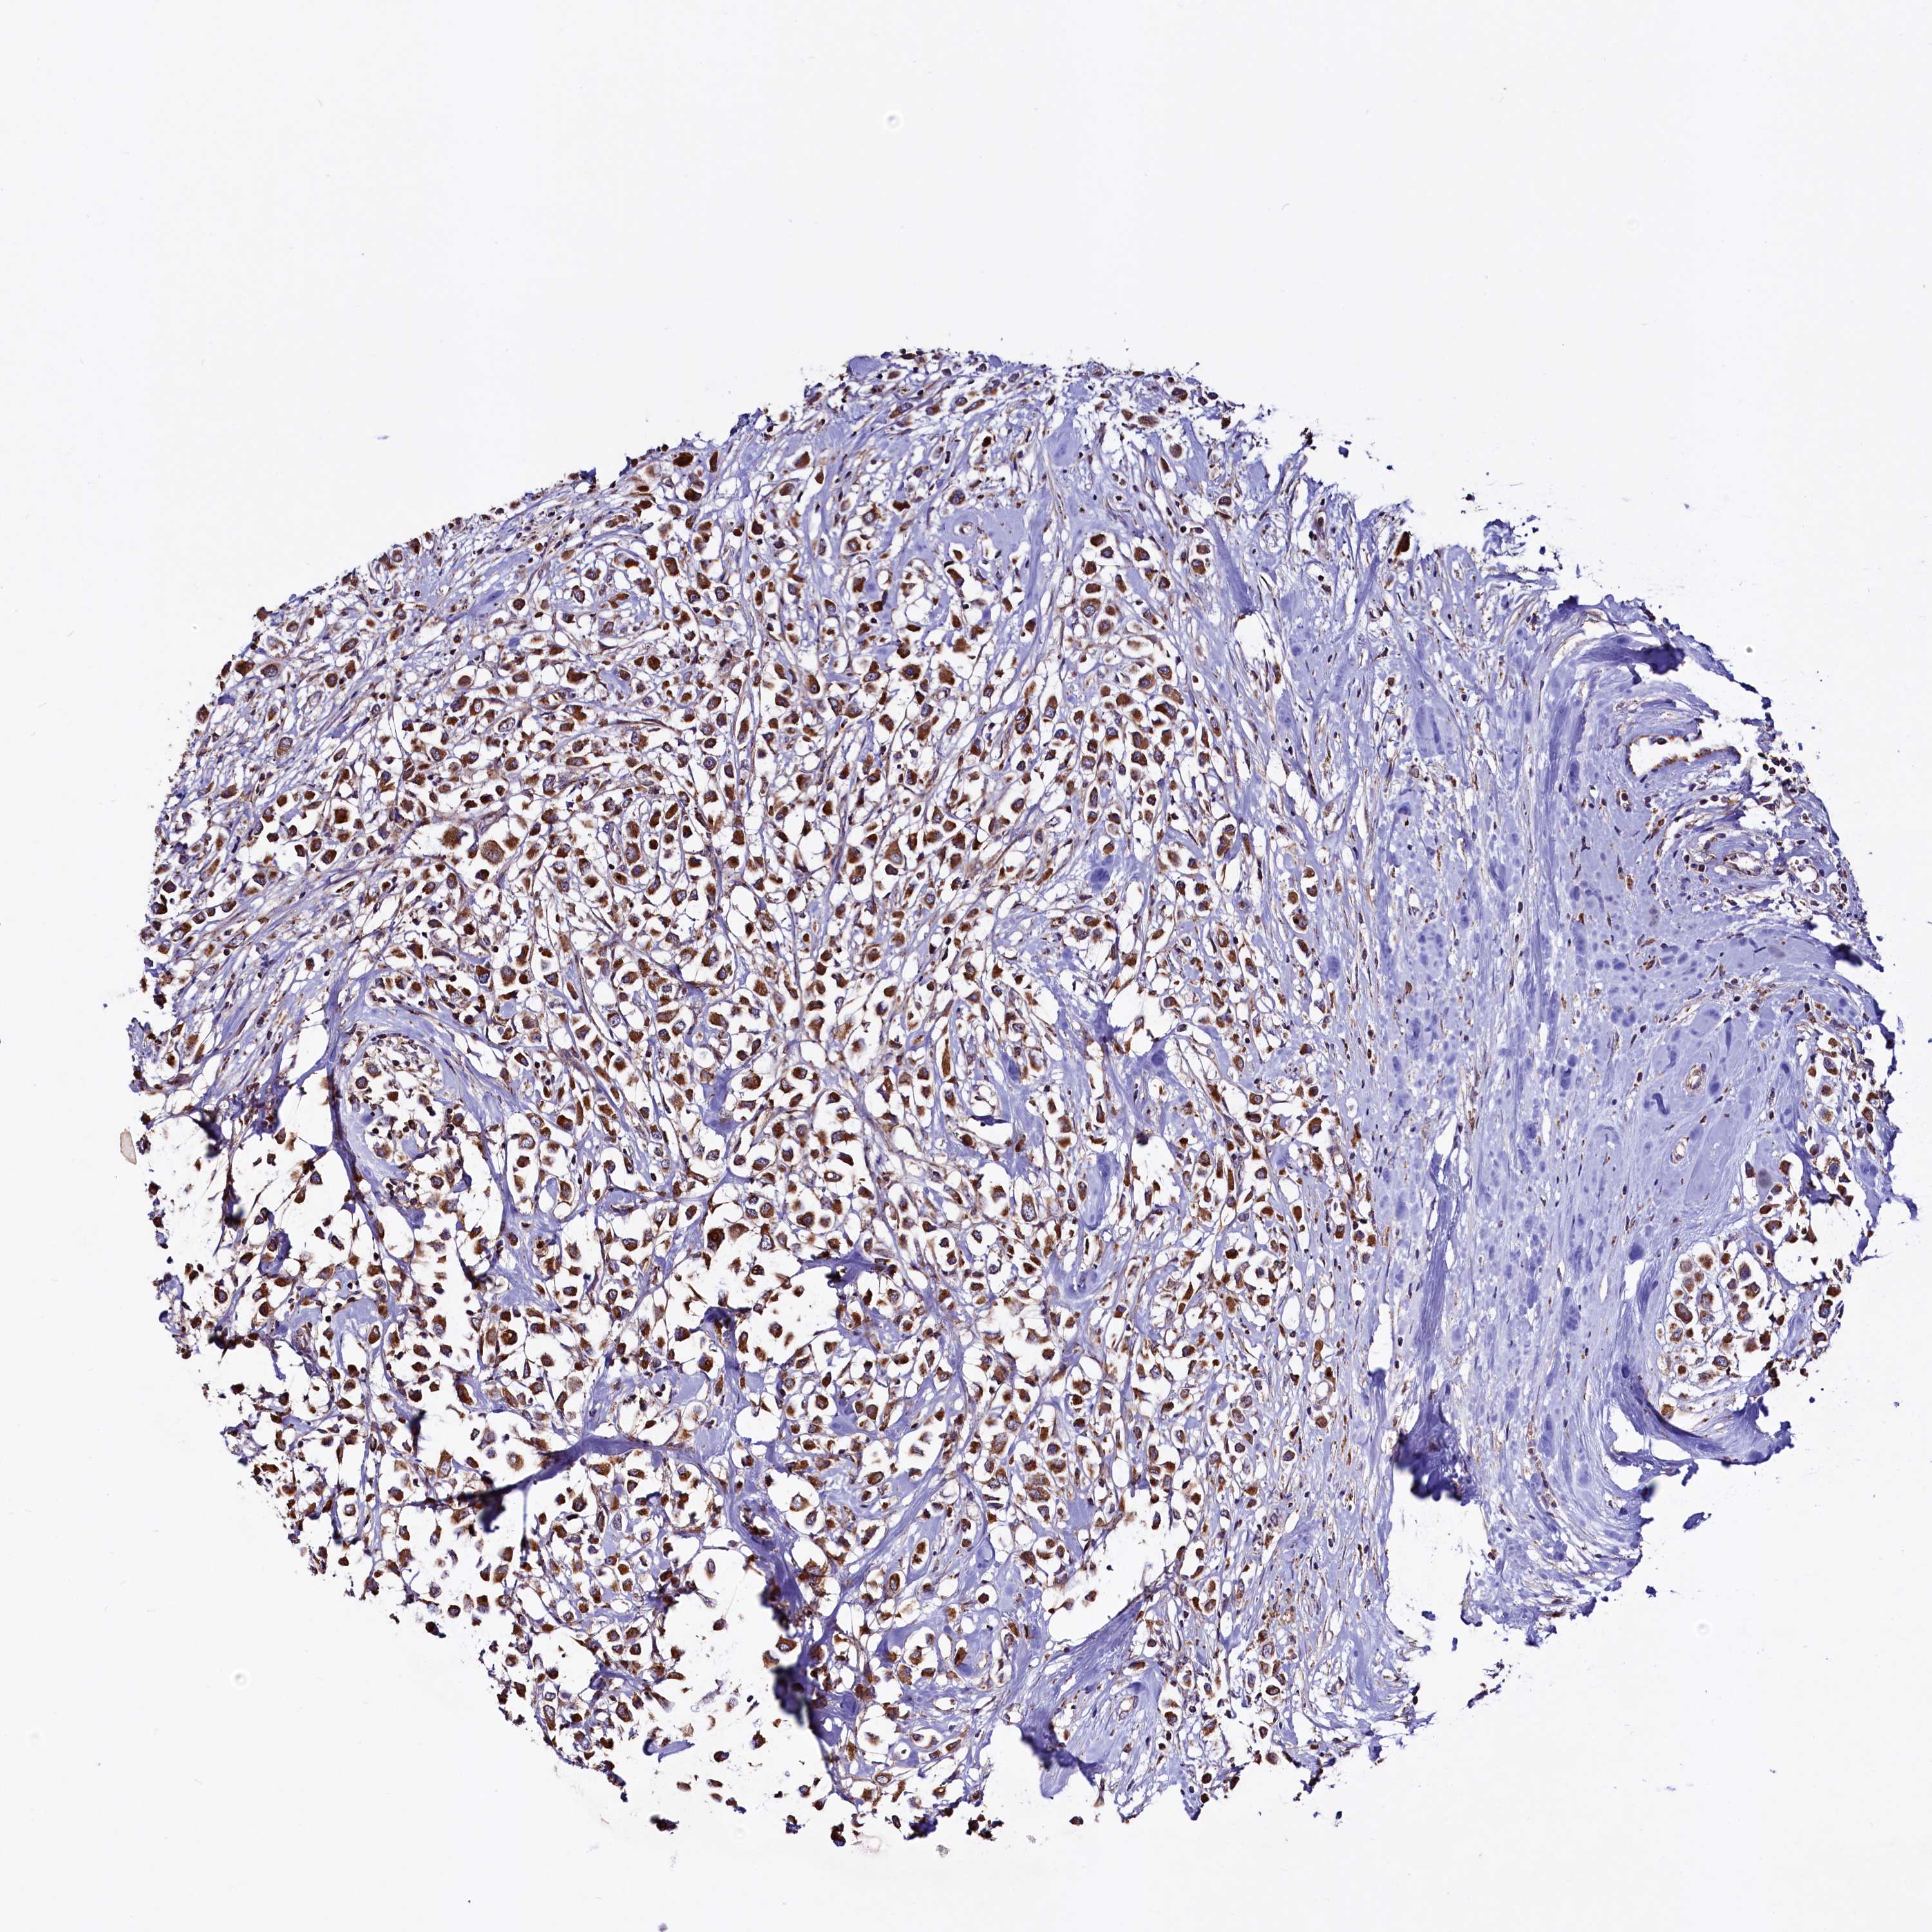

CANCER BREAST CANCER Show tissue menu

BRCA TCGA BRCA VALIDATION PROTEIN EXPRESSION

ANTIBODIES

AND

VALIDATION